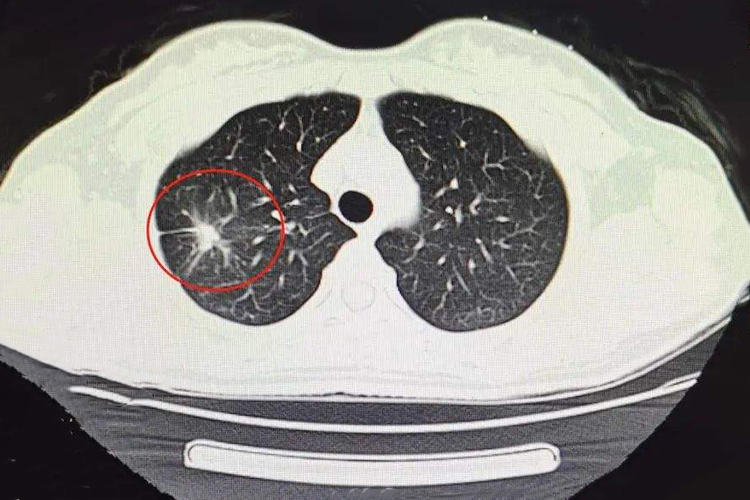

肺结核治好后的疤痕,在影像学检查下可表现为结节、斑块、条索状致密影,一般是肺部在修复愈合过程中纤维成分代替细胞成分引起。

肺结核治好后的疤痕,在影像学检查下可以看到有结节、斑块、条索状的致密影,也可呈现网状、线状、蜂窝状等其他不同的形态。